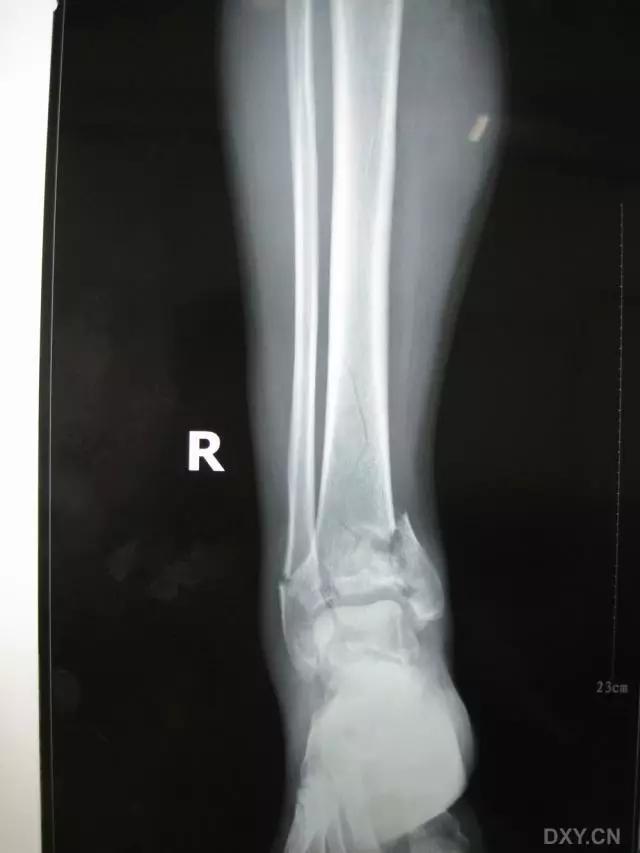

10. Gosselin 骨折

胫骨远端的 V 字形骨折,延伸至踝关节。

(来源:RadioGraphics)

6. Pilon 骨折

涉及负重关节面(胫距关节面)与胫骨远侧干骺端的骨折。其典型特征是干骺端存在不同程度的压缩、干骺端的压缩粉碎性骨折不稳定、原发性关节软骨损伤以及永久性关节面不平整导致预后不良。

pilon 骨折正位片

pilon 骨折侧位片